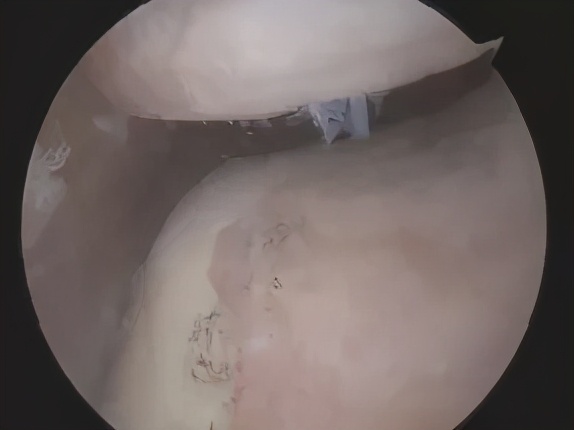

内侧半月板损伤

半月板是膝关节内一个“垫片”结构,起到缓冲、稳定关节的重要作用。因此,一旦内侧半月板出现撕裂,就会出现4号位和偏内后侧的长期疼痛。

最常见于长期需要下蹲的职业,如木工、水电工、泥水匠等,年轻人多是在剧烈运动,如踢足球、打篮球等时,膝关节屈曲高速旋转,从而造成内侧半月板损伤。如果半月板损伤严重,时间长了可能需要手术切除。切除后,骨头跟骨头硬碰硬,就像光脚走路似的,软骨磨损也会加快。所以,大家一定要注意保养好半月板!

如果青少年出现5号位的疼痛,并且有关节内弹响、偶尔关节卡锁的症状,就非常有可能是外侧先天性盘状半月板撕裂。简单来说,就是外侧半月板发育的太大太厚了(亚洲人非常常见),就容易在膝关节扭转时发生撕裂。一旦撕裂,关节功能影响较大,通常需要关节镜手术修复。